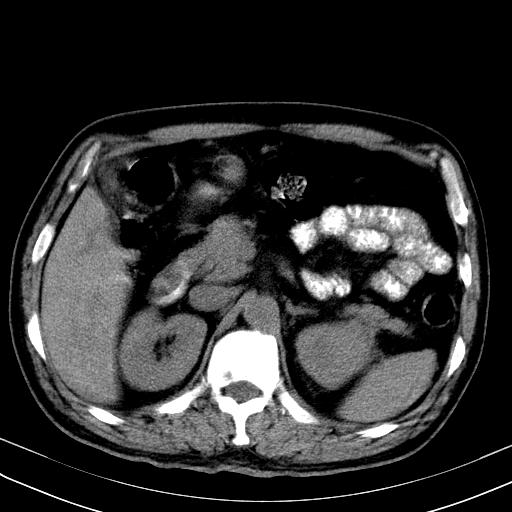

先行ct平扫,纵膈内多发软组织影,ct值约为36hu,以下为增强扫描和腹部平扫。

经典?纵膈多发肿大淋巴结。腹膜后未见异常。

还见胃窦壁增厚!转移亦有可能!

多发肿大淋巴结影,肝内改变需结合强化观察